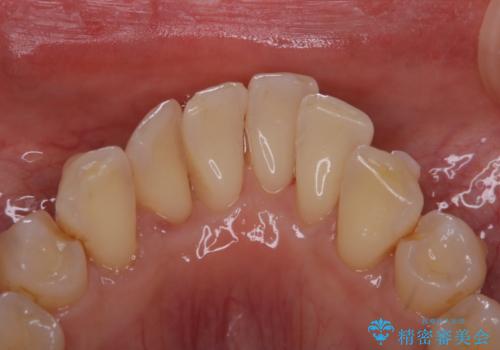

インビザライン中の歯石取り PMTC

- インビザライン治療中のお口の中の汚れが気になるとのことでした。PMTC30分コースを行いました。

インビザライン矯正治療中は、ご自身の歯にアタッチメントという突起物(効率的に歯の移動を行うため)をつけます。そのため、通常時よりも歯石やステインが付きやすい状態になることがあります。

インビザラインは透明なマウスピースなので、ご自身の歯に歯石やステインなどが付着していると、見た目に影響してしまうことがあります。

矯正治療中の虫歯・歯周病・口臭予防としても、定期的にPMTCを行うことが大切です。